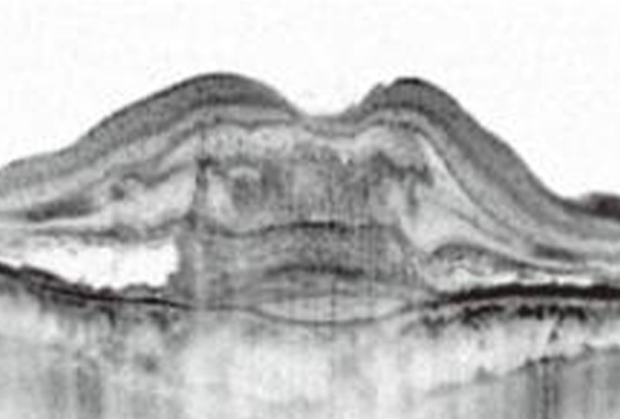

網膜の断面の状態を調べる検査で、脈絡膜新生血管や網膜のむくみなどが観察できます。

正常なOCT画像

加齢黄斑変性のOCT画像